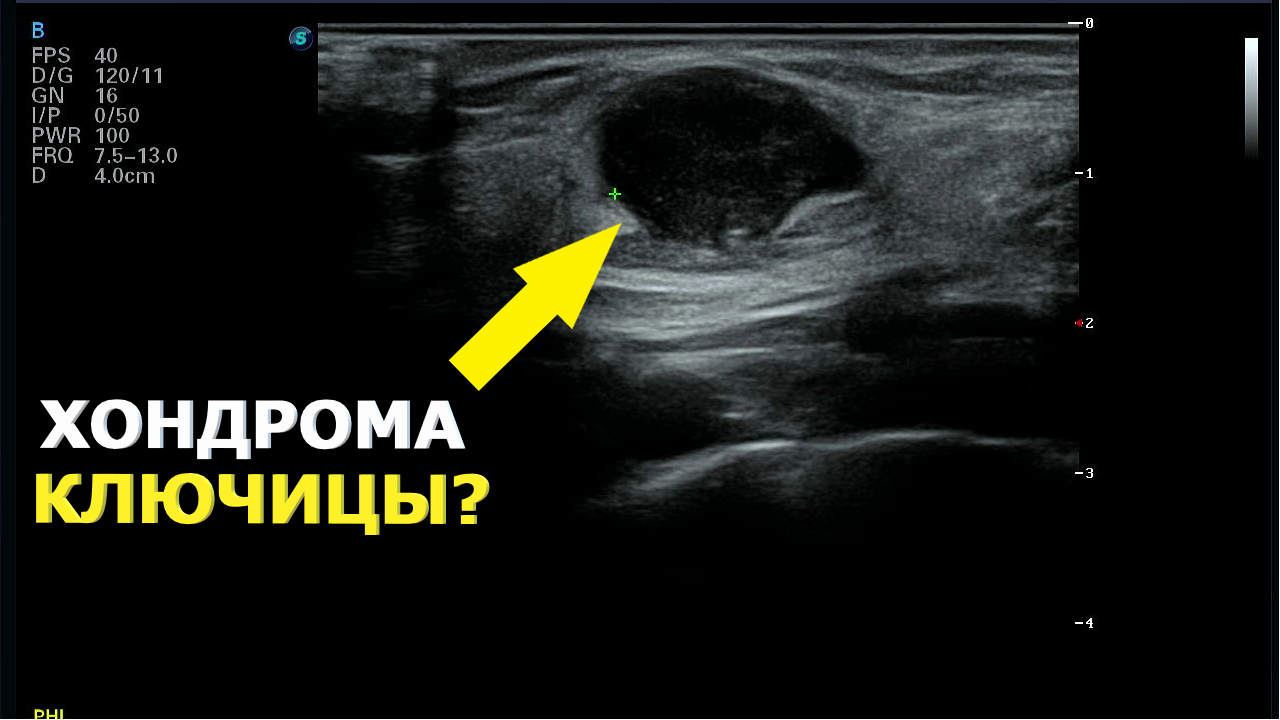

Коллеги разбираем случай. Женщина 40 лет пришла на плановое УЗИ ОБП без жалоб. Я увидел кисты в печени предложил посмотреть почки и там тоже кисты. Что вы увидите: - Кисты печени не менее 8 штук самая крупная 1311 мм - Кисты почек не менее 56 в каждой самая крупная 38 мм - Цветной допплер: кисты не окрашиваются - Полипы желчного пузыря 3 штуки до 6 мм кровоток не зарегистрирован - Нормальные поджелудочную железу селезёнку и малый таз Для УЗИ-врачей: при случайных кистах в одном органе всегда проверяйте другой. АДПКП системное заболевание не пропустите. Голосовой помощник для врачей Medmate протокол УЗИ за 30 секунд: Telegram: MAX: YouTube: ВК Видео: Сайт: Подписывайтесь на наши основные площадки с разборами УЗИ и хирургии: ВК Видео: YouTube: RuTube: Telegram: MAX: УЗИ поликистоз поликистозпечени поликистозпочек АДПКП кистыпечени кистыпочек ультразвуковаядиагностика medmate,